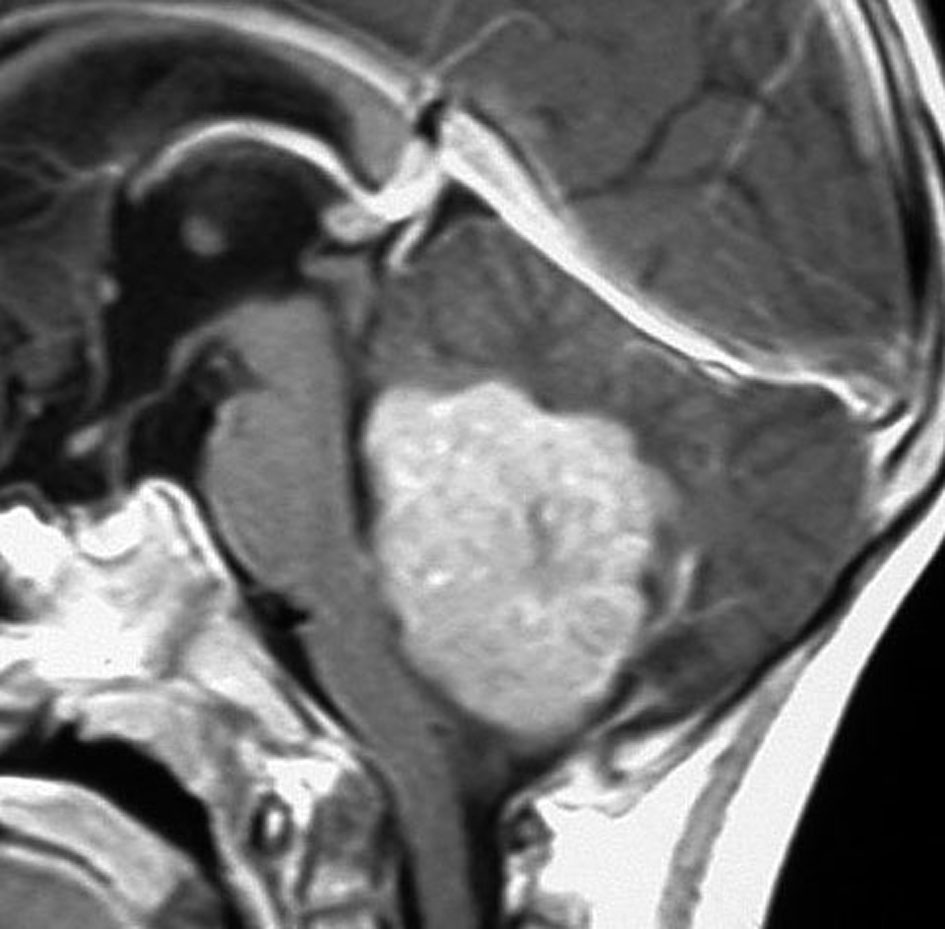

- MRIで診断します

- 境界がはっきりした腫瘍です,くりんとしています

- ガドリニウム造影剤で白く映ります(増強される)

- でも,ガドリニウム造影剤が入らなくて白く映らないものもあります

典型的な小脳虫部(小脳の真ん中)の髄芽腫です。横の方,ルシュカ孔へ伸びていないので上衣腫と区別できます。ガドリニウムという造影剤で白く写っています。